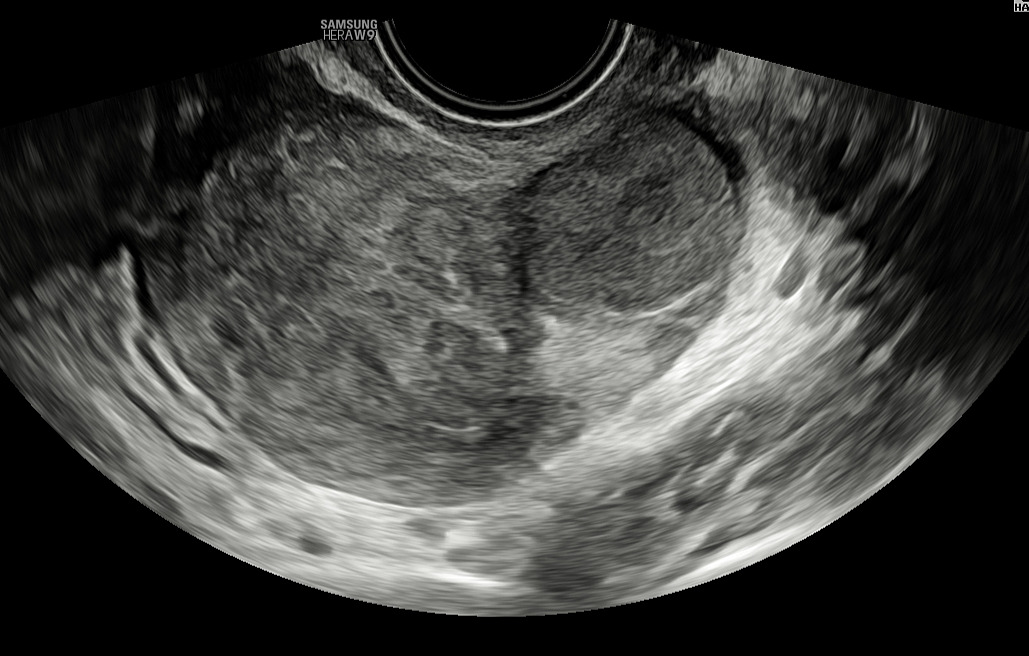

On ultrasound examination, typical endometriomas present as a cystic lesion with ground-glass echogenicity, with one to four locules and no solid components in a premenopausal patient (Figure 26). Of 713 histologically confirmed endometriomas in the International Ovarian Tumor Analysis (IOTA) studies, 65% were unilocular and 73% exhibited ground-glass echogenicity and 13% had low-level echogenicity.42 Atypical endometriomas are defined as unilocular-solid lesions with ground-glass echogenicity and a papillary projection, a color score of 1 or 2 and no vascularization inside the papillary projection (Figure 27).5 As per the recommendation of the IDEA consensus, the presence or absence of endometriomas should be described, as well as their number, size in three orthogonal planes and their ultrasound appearance according to International Ovarian Tumor Analysis (IOTA) terminology.43 Assessing vascularization by power Doppler may help in the differentiation between an endometrioma, a corpus luteum and a malignant lesion.44 A corpus luteum is characterized by strong circumferential blood flow (‘ring of fire’) and will generally resolve spontaneously after the menstrual cycle, unlike an endometrioma.

26

Ultrasound images of endometriomas with typical features of ground-glass echogenicity, up to four locules and no solid components.